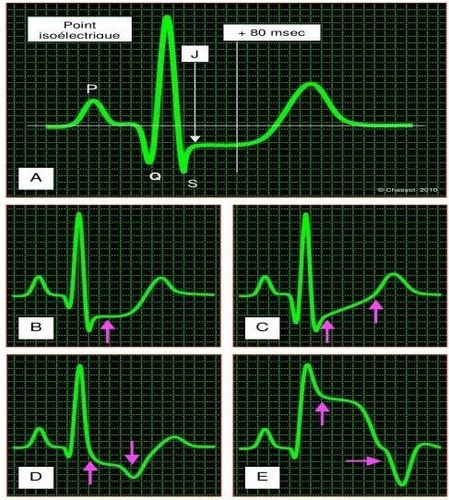

Giá trị của đoạn ST được đo 60-80 msec sau điểm J (điểm nối giữa sóng S và đoạn ST). Tiêu chuẩn thiếu máu cục bộ:

- Chênh ngang hoặc hướng xuống dưới 1,0 mm (> 0,1 mV);

- Chênh xuống chậm hơn 2 mm (> 0,2 mV);

- Chênh lên quá 1 mm (> 0,1 mV).

Phép đo có liên quan hơn ở 80 msec từ điểm J, nhưng được rút ngắn 60 msec trong trường hợp nhịp tim nhanh (tần số> 100 nhịp / phút). Biên độ và mức độ của ST chênh tỷ lệ thuận với khối lượng cơ tim thiếu máu cục bộ.

Độ đặc hiệu của độ chênh ST đối với thiếu máu cục bộ cơ tim rất cao, nhưng thay đổi tùy theo hình dạng của phân khúc: từ 95% cho ST chênh xuống, nó tăng lên 85% cho một ST chênh xuống thay đổi theo chiều ngang và đến 75% cho một sự thay đổi ST chênh hai pha.